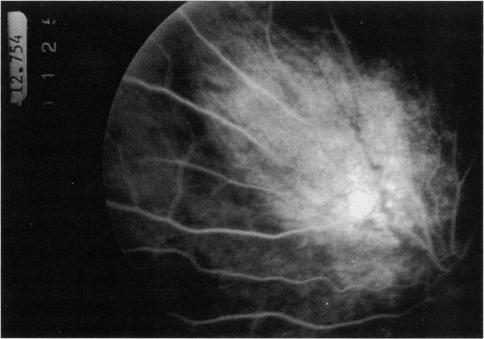

We identified five patients with the organoid nevus syndrome. Four had a classic sebaceous nevus in the facial and scalp area, and 2 had seizures and arachnoid cysts. All 5 patients had an epibulbar tumor, which proved to be a complex choristoma in one case that was studied histopathologically. A characteristic ophthalmoscopic feature, observed in the 4 patients with clear ocular media, was a flat yellow discoloration of the posterior fundus, of variable size and shape, which appeared to correlate with a dense plaque noted on ultrasonography and computed tomography. In 1 case, histopathologic examination showed that this posterior lesion contained intrascleral cartilage.

Our observations and a review of the literature indicated that the organoid nevus syndrome has varied manifestations. Like the closely related phakomatoses, it often occurs as a forme fruste, without full expression of the syndrome. The most important ocular manifestations are an epibulbar mass, compatible with a complex choristoma, and focal yellow discoloration in the fundus, probably related to intrascleral cartilage.

我们确定了5例器官样痣综合征患者。4例在面部和头皮区域有典型的皮脂腺痣,2例有癫痫发作和蛛网膜囊肿。所有5例患者均有眼球表面肿瘤,其中1例经组织病理学研究证实为复合性脉络膜瘤。在4例眼介质清晰的患者中观察到一个特征性的眼底镜特征,即眼底后部有扁平的黄色变色,大小和形状各异,这似乎与超声检查和计算机断层扫描中发现的致密斑块相关。在1例中,组织病理学检查显示该后部病变含有巩膜内软骨。

我们的观察和文献回顾表明,器官样痣综合征有多种表现。与密切相关的错构瘤一样,它常以不完全型出现,综合征未完全表现出来。最重要的眼部表现是与复合性脉络膜瘤相符的眼球表面肿块,以及眼底的局灶性黄色变色,可能与巩膜内软骨有关。